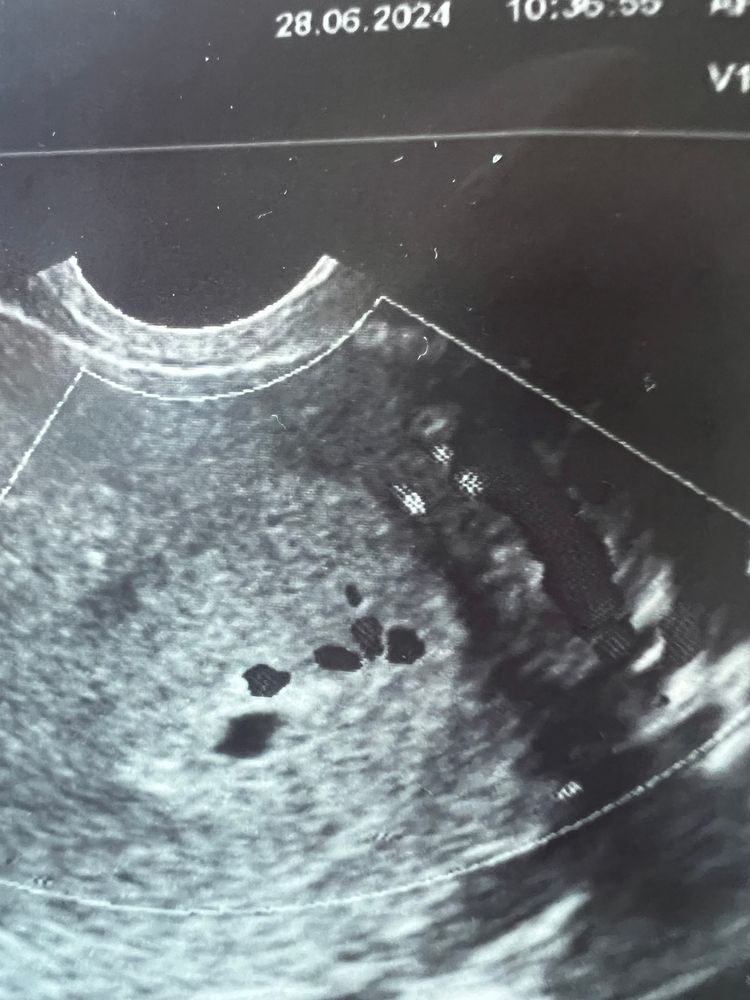

УЗИ 4-5 недель: угроза, деформация п/я, точки и кисты

Но вопрос в другом, что с УЗИ? Что за многочисленные точки … врач предположила кисты до 5 мм, но не точно

Я бы переделала ,очень странные точки . С такими четкими границами ,может аппарат хреновый. Сходите в другую клинику через 5-6 дней)